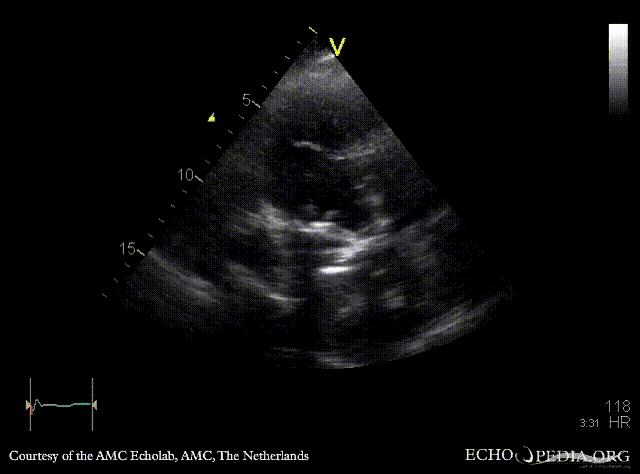

Case 108